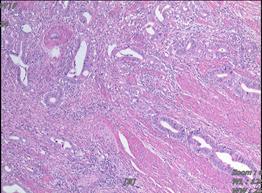

术后病理(2019.6)

2019-6-19在全麻下行腹腔镜下腹会阴联合直肠癌根治+阴道后壁切除术。术后病理示:溃疡型中分化腺癌,癌组织累及周围结缔组织;脉管及神经侵犯;上、下切缘及环周切缘阴性;检出肠系膜淋巴结(4/7枚)见癌转移,临床另送“主淋巴结”镜下为纤维结缔组织,未见淋巴结结构;阴道后壁查见癌累及。基因检测:不存在错配修复功能缺陷(dMMR)。KRAS、NRAS、BRAF基因V600E:均未见突变。